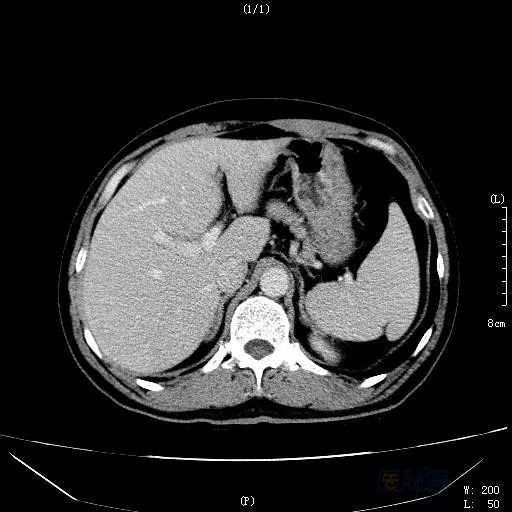

之后,患者电话笔者申请会诊,赴约。仔细阅读病例病史,发现患者并无既往肝病史,乙肝两对半、丙肝等检查无阳性结果,无饮酒等嗜好;患者虽似乎有肝衰竭的症状表现,但凝血指标基本正常,经过保肝治疗,病情也明显好转。阅读CT、MRI发现:肝左内叶见一高密度影,但三期无明显变化,肝脏体积偏大,呈不均质改变,MRI提示非脂肪病变,肝静脉显示不清。此时,笔者心里基本有了答案,随后追问患者病史,立即带回我院。患者经治疗三个月后,肝脏密度逐渐正常,原来的占位病灶消失(见图3)。

图3 治疗三个月后CT延迟期扫描

该患者在入院两个月前不慎摔伤,已自服“三七粉”(三七为自己种植)40天,甚至住院期间仍然服用。影像学提示肝脏呈淤血性改变,所谓的占位性病变其实是“肝岛”。这是一例肝窦阻塞综合征(hepatic sinusoidal obstruction syndrome,HSOS)患者——HSOS又称肝小静脉闭塞病(hepatic veno-occlusive disease,HVOD)。

患者经过抗凝治疗,病情得到控制,基本治愈。三个月后,我们再次做肝穿刺病理学检查(见图4)。根据病理表现,发现继续抗凝治疗已经难以改善中央静脉闭塞,因此停用抗凝药物。